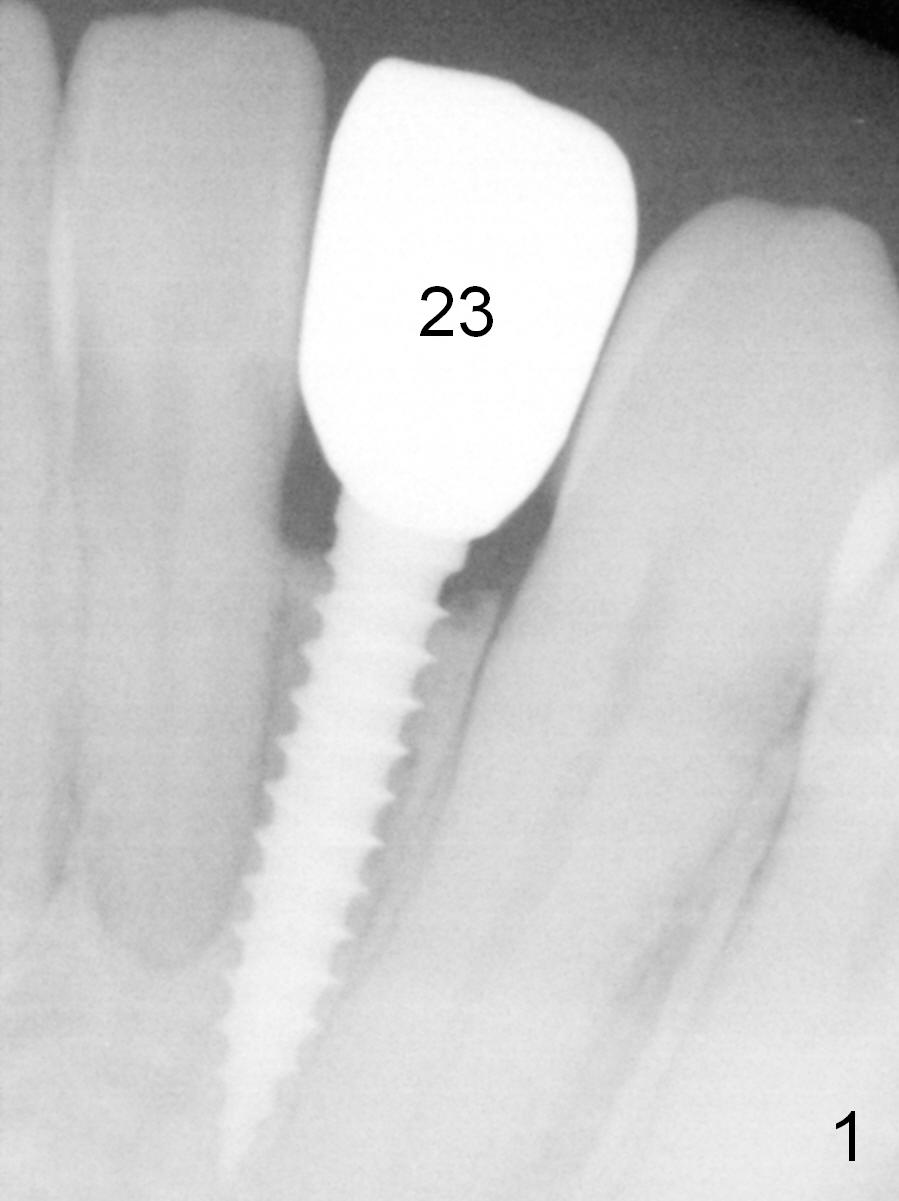

Make a new crown less transparent than the previous one (Fig.3). Can you block inside the crown to take care of the metal shade of the abutment/implant?

The original shade is A 2.5 (enclosed in the case).

Choose a shade a little darker and more yellowish (Fig.4-7 before

cleaning; Fig.9-11 after cleaning). It

appears that there is a change in shade of crown over the time.

The patient is sure that the original shade was alright, but over the

time the shade changes. I wonder

whether it is due to stain/paint to the crown in the lab.

Can you choose a Zirconia block that has the closest shade?

Do not stain or paint the crown.